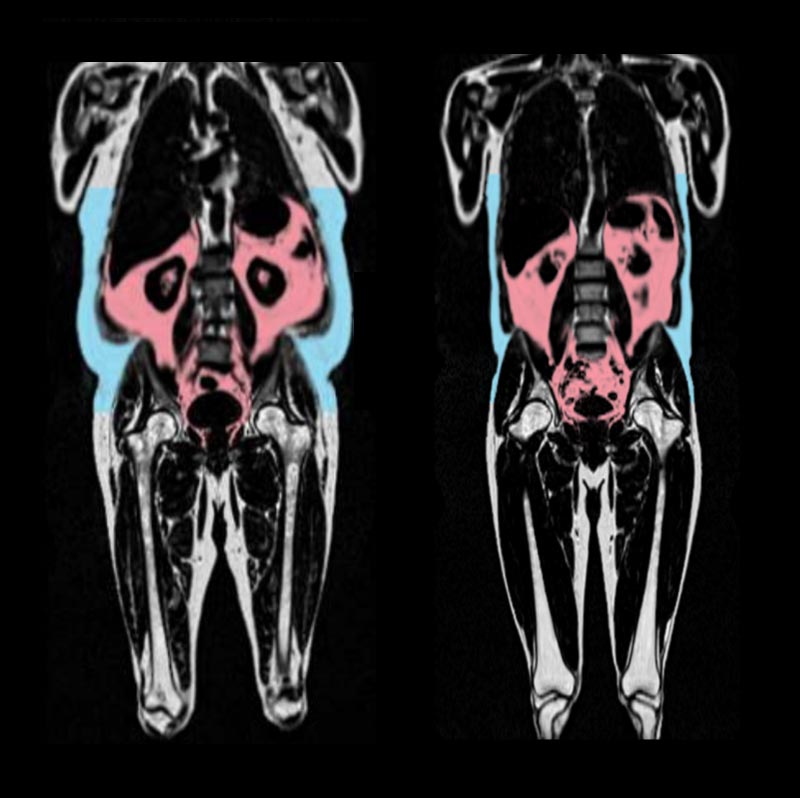

Вісцеральний жир — це «глибокий жир», що накопичується навколо внутрішніх органів у черевній порожнині, таких як печінка, шлунок і кишечник. Він невидимий неозброєним оком, тому його присутність важко виявити без спеціальних методів візуалізації. Як стверджує професор Деклан О’Реган, «поганий жир, прихований глибоко навколо органів, прискорює старіння серця». Саме цей тип жиру, за даними дослідників, найтісніше пов’язаний із жорсткістю та запаленням серцевих тканин, що є основними ознаками його старіння.

Науковці з Лондонської лабораторії медичних наук MRC використовували штучний інтелект (ШІ), щоб встановити так званий «вік серця» – умовний показник біологічного стану серця, що порівнюється з фактичним віком людини. У ході аналізу понад 21 тисячі зображень з UK Biobank було виявлено: чим більше вісцерального жиру, тим «старше» серце. Важливо, що індекс маси тіла (ІМТ) не показав високої точності в передбаченні віку серця. «ІМТ не є хорошим способом прогнозування віку серця», – наголосив О’Реган, підкреслюючи значення точного вимірювання розподілу жиру.

Виявлені гендерні особливості у розподілі жиру свідчать про глибші біологічні механізми. У чоловіків жир переважно накопичується в області живота, що формує так звану «яблукоподібну» фігуру, яка виявилась фактором ризику. Жінки ж частіше мають «грушоподібну» форму тіла – жир відкладається на стегнах і сідницях, і цей тип розподілу, за словами вчених, може захищати серце.

«Жир навколо стегон і сідниць у жінок може сповільнювати старіння серця», — зазначив О’Реган. Це пояснюється, зокрема, впливом гормону естрогену. У жінок у передменопаузі спостерігалося менше вікових змін серця, що дозволяє припустити: естроген може відігравати захисну роль у серцево-судинному старінні. Професор Брайан Вільямс також наголосив: «Оскільки характер розподілу жиру, який зазвичай спостерігається в організмі жінок, пов’язаний з естрогеном, цей гормон може стати ключовим у розробці майбутніх методів лікування старіння серця».